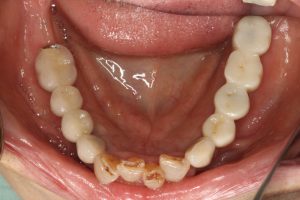

再度右下3本と、左下1本インプラントを入れて無事治療は終了しました。

そして3ヶ月たった本日。定期検診にいらしていただきました。